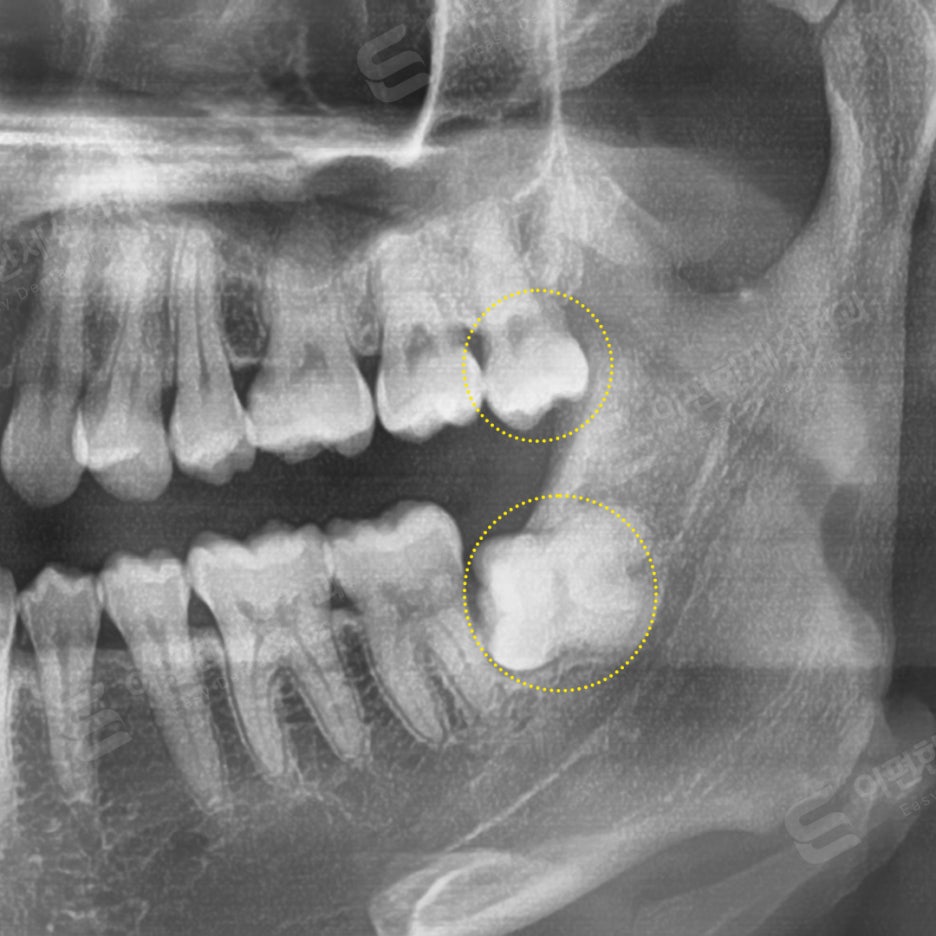

촬영 일자 24.02.16

사랑니 잇몸 통증 호소 발치 케이스

#38 완전매복 발치

#28 일반 발치